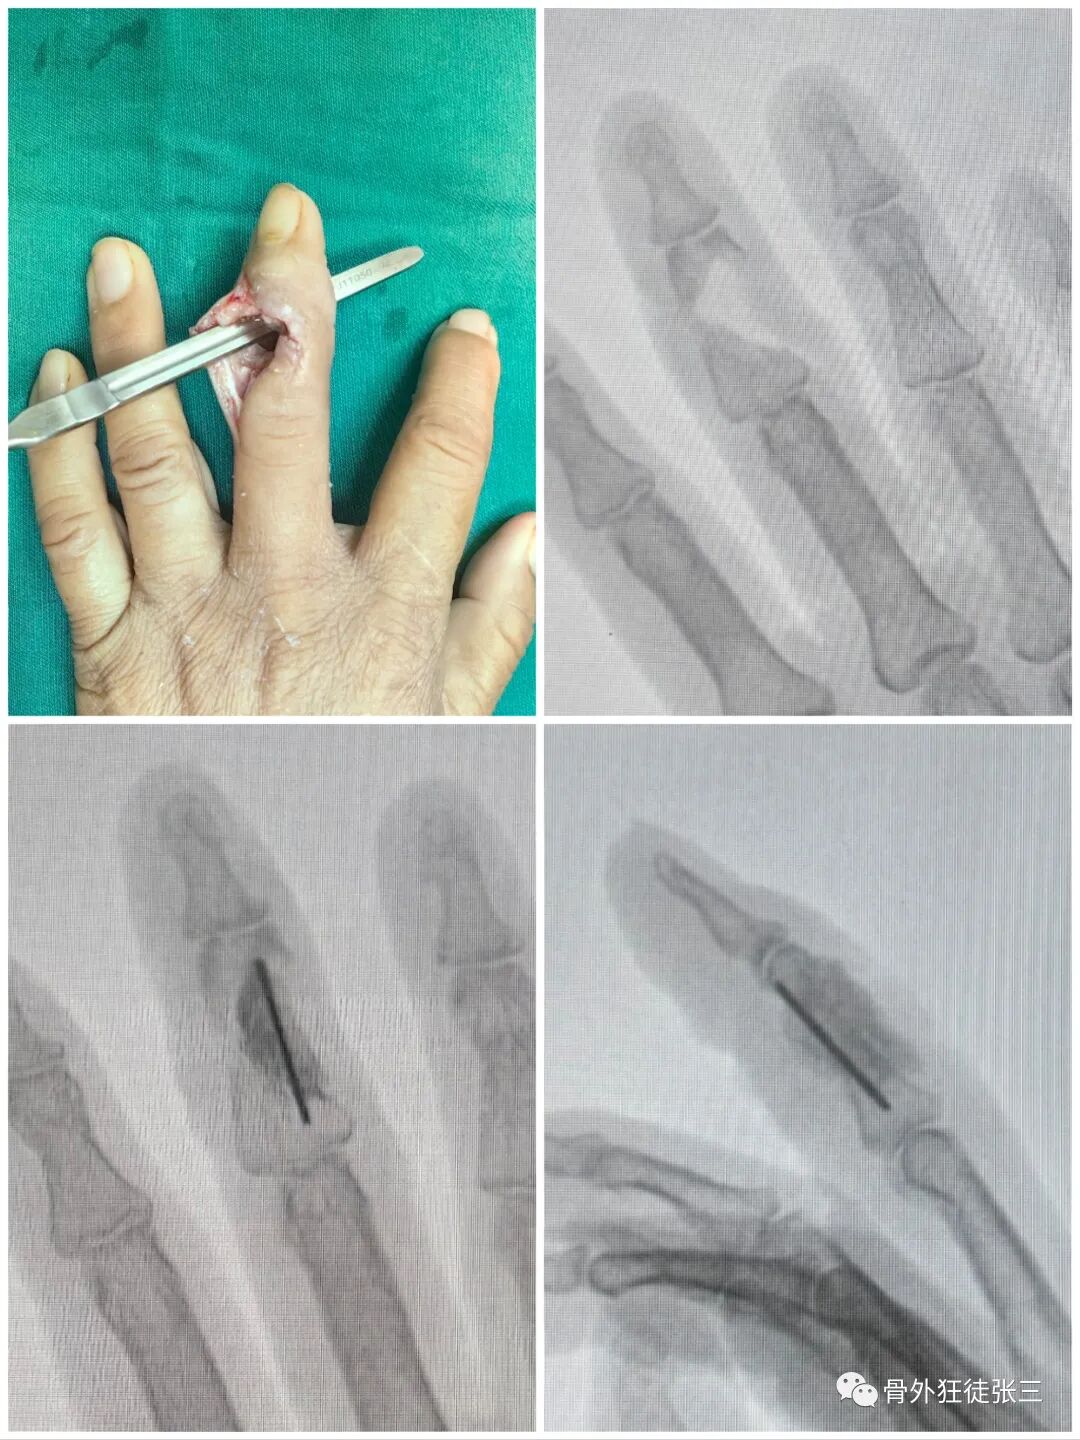

病例5,开放性第3、4掌骨骨折,隔山打牛,克氏针支架。

病例7,开放性掌骨,指骨骨折,克氏针内固定